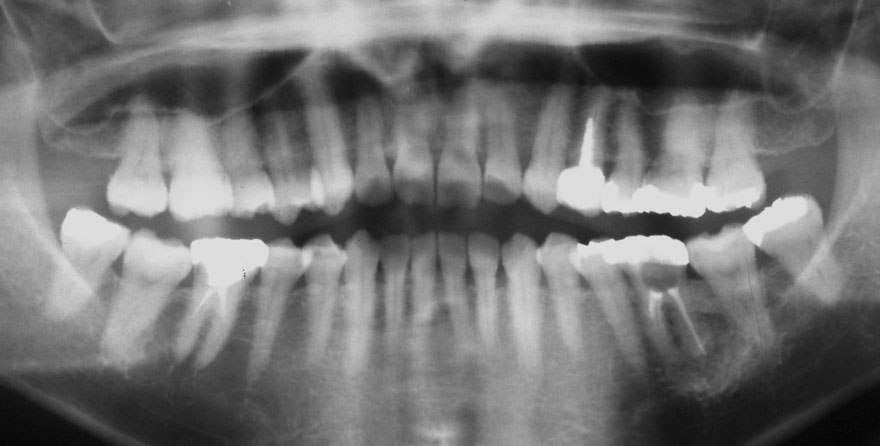

初診時 36歳 女性 平均歯槽骨喪失量:2.70mm

30年後 66歳

平均歯槽骨喪失量:3.26mm

30年間喪失量:-0.55mm

年間喪失速度:-0.018mm

(ケア頻度:3.01ヵ月ごと)